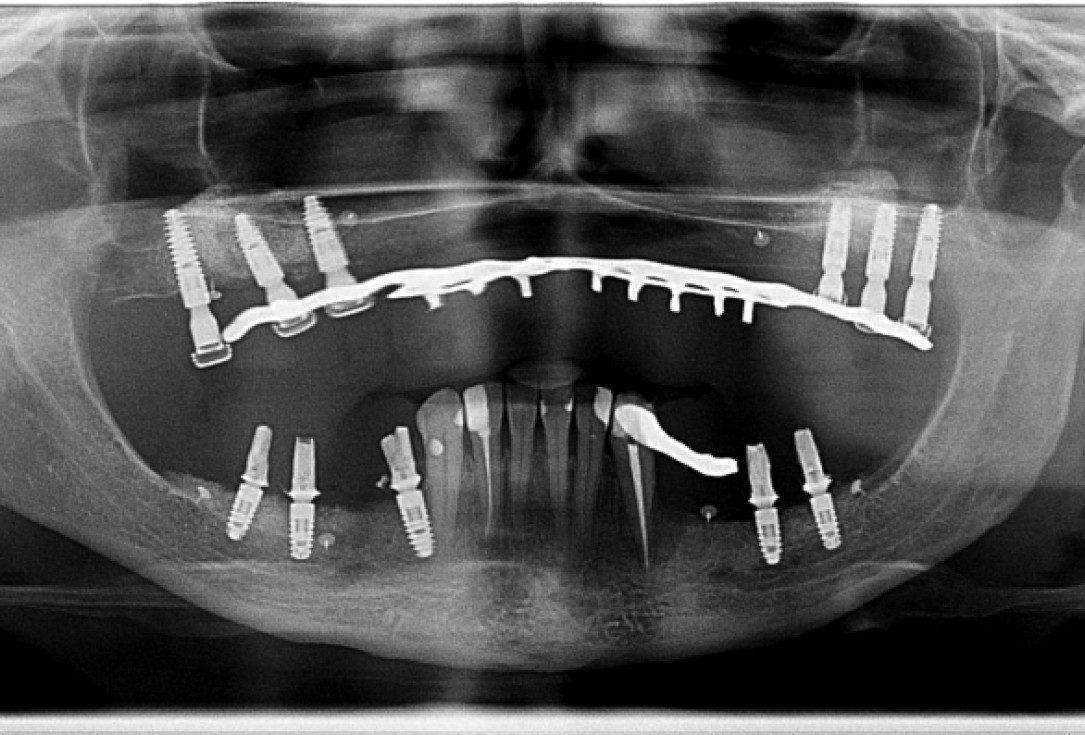

18/18 - X-ray scan 9 months post-op: Full integration of maxgraft® bonering and implants and proceeding remodeling of the grafts